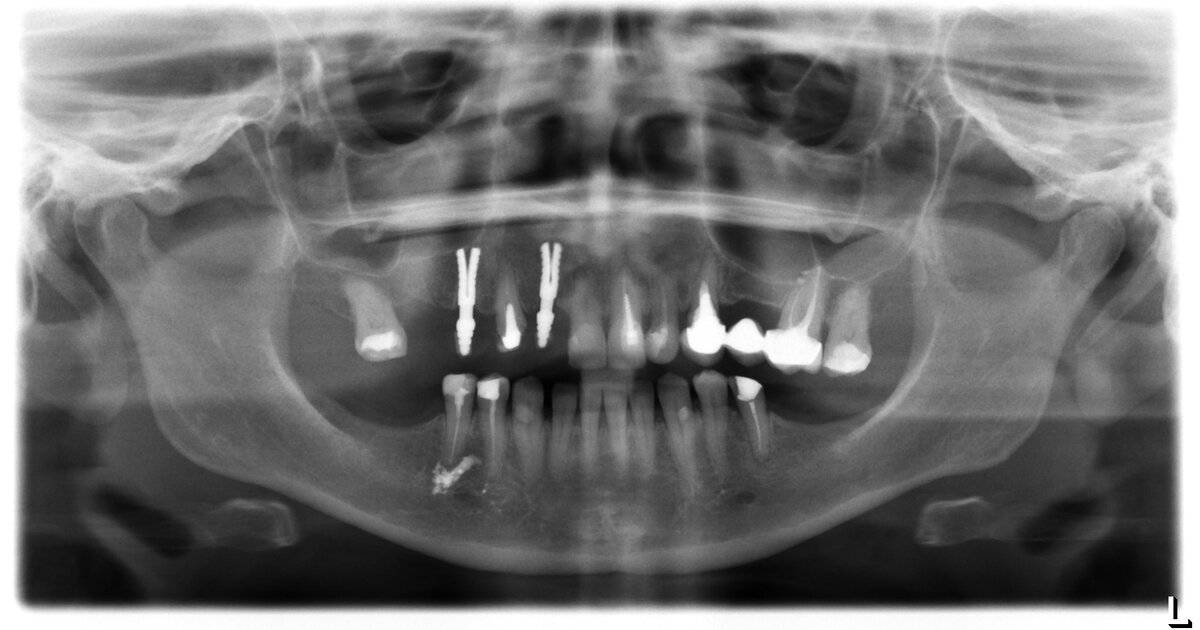

Давайте разберем снимок подробно:

1. Установлены 2-а неизвестных импланта

2. Отсутствуют жевательные зубы (шестые и седьмые) на нижней челюсти

3. Установлен мостовидный протез на зубах верхней челюсти. Коронки на опорных зубах нависают. Атрофия кости возле опорных зубов на 1/3 длины корня.

4. Большие композитные реставрации (пломбы)

Посмотрите, в боковых отделах нет основных жевательных зубов – шестых и седьмых, из этого следует, что пациент будет пережевывать пищу теми зубами, которые остались. Неминуемая перегрузка приведет к разрушению коронок, резорбции кости вокруг имплантатов, возможно поломке имплантатов, сколу больших композитных пломб, наклонам и сдвигам зубов, и разрушению мостовидного протеза.